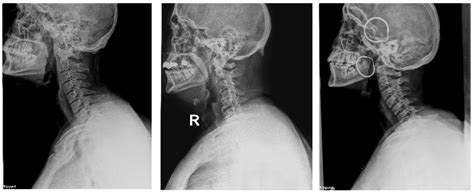

• cervical dislocation symptoms

• cervical vertebrae dislocation

• cervical dislocation definition